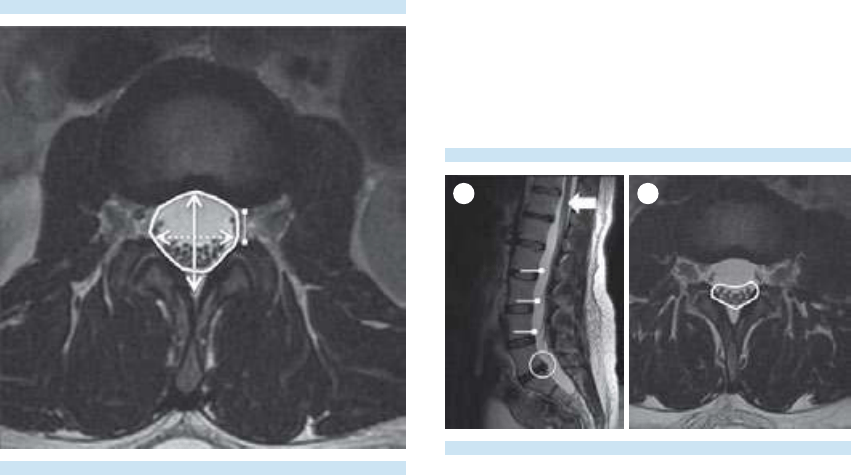

3. Evaluación del disco intervertebral.

4. Evaluación de las articulaciones face-

tarias, láminas, pedículos, procesos

transversos y espinosos; del canal central

y los recesos laterales.